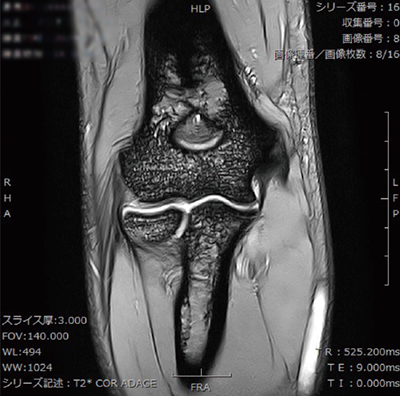

■症例3:右肘内側側副靭帯画像

T2*強調画像,TR/TE:525/9,スライス厚:3mm,FOV:140,マトリックス:300×300,DLR:Medium,VIVID:2,Mode:iRCM,撮像時間:2:04